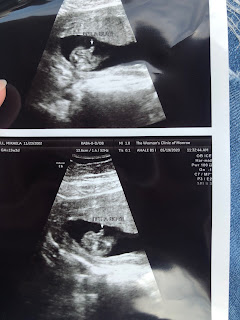

We went to her appointment yesterday. Everything looks good so far! His heart rate was 160, and he was wiggling around and showing off for the ultrasound. She goes back in four weeks for the anatomy scan. She's almost 16 weeks pregnant! She has decided to name him Daniel.